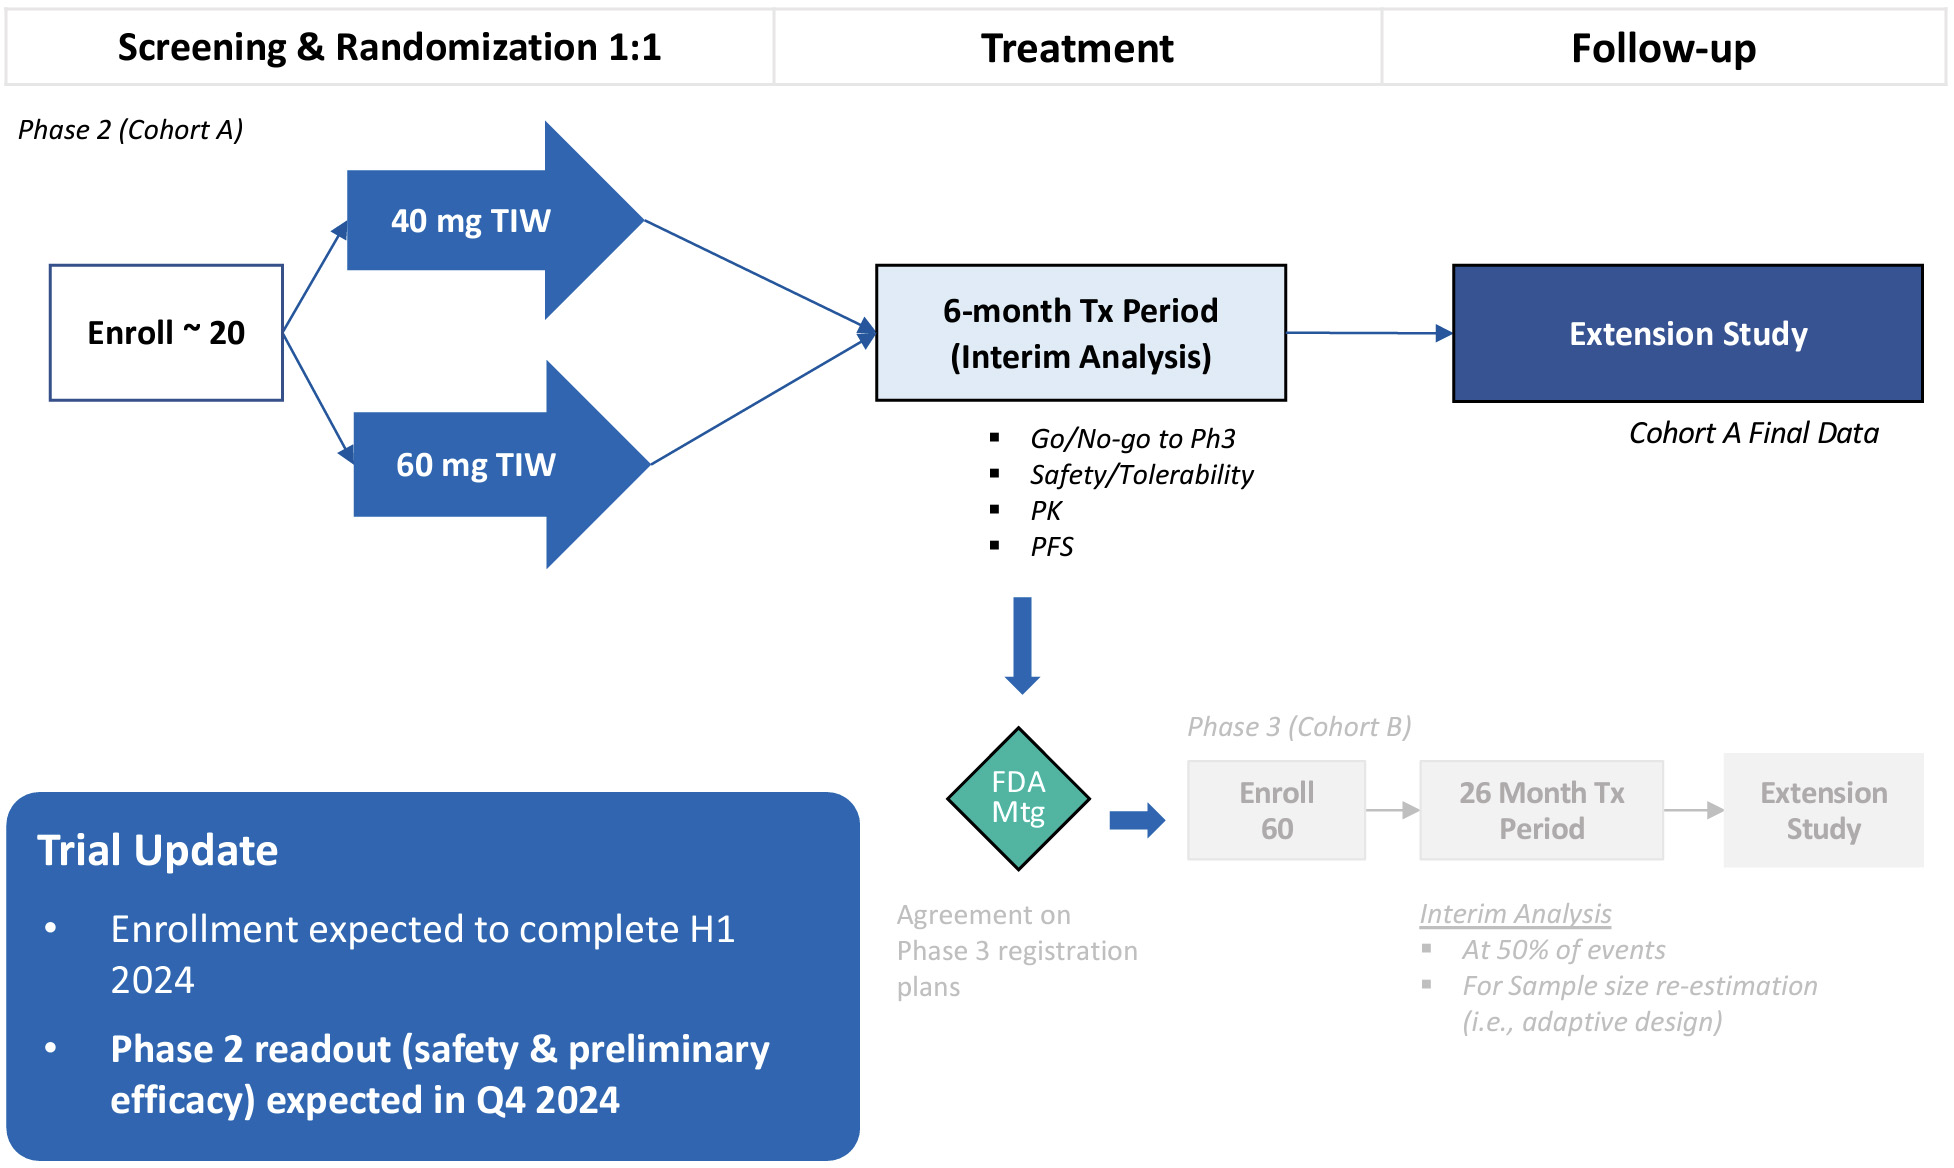

•Five phase 2 clinical-stage programs with multiple upcoming data readouts expected, including REC-994 in cerebral cavernous malformation (CCM) in Q3 2024, REC-2282 in neurofibromatosis type 2 (NF2) in Q4 2024, REC-4881 in familial adenomatous polyposis (FAP) in H1 2025, and REC-4881 in AXIN1 or APC mutant solid tumors in H1 2025